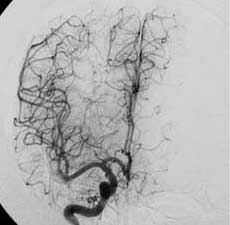

二、脑动静脉畸形(AVM)

---- Spetzler对AVM的分级方法已越来越多地被人们接纳和采用。脑AVM最危险的症状之一是出血。AVM每年的出血率为 3%~4%,第一年内再出血约6%。每次出血的致残率为30%,病死率为12.5%,而积极治疗的总残废率加病死率在10%以下。

---- 血管内栓塞对于单支或少数供血动脉的AVM,特别是新近出血的病例,可以达到微侵袭、痛苦小、疗效迅速的目的。 近来改变栓塞方式,将导管直接放置 畸形血管团内,注射NBCA胶,可使畸形团的解剖 治愈率提高至27%。再加上更细、超 滑的微导管问世,栓塞的并发症更为降低。针对大型、功能区 的AVM栓 塞可缩小其体积,改善血液动力学分布,以利于显 微外科技术切除或放射外科治疗,是后二者的重要辅助手段。